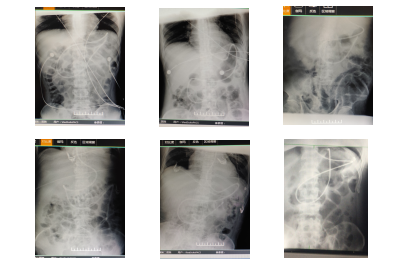

《导管去哪儿了——肠内营养管的X线定位判读》专题讲座